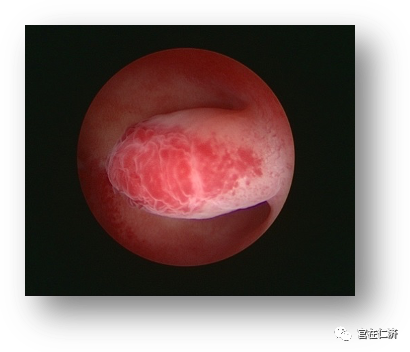

4. Q: 内膜息肉怎么明确诊断?

A:诊断性宫腔镜是最准确的诊断方法,并可以同时评估病变的大小和特性。此外常用的诊断方法还有经阴道超声检查,子宫输卵管碘油造影,盆腔核磁共振等。我们中心采用2.9mm口径的Trophy诊断镜,无需麻醉,没有性生活的病人也可以进行诊断操作。